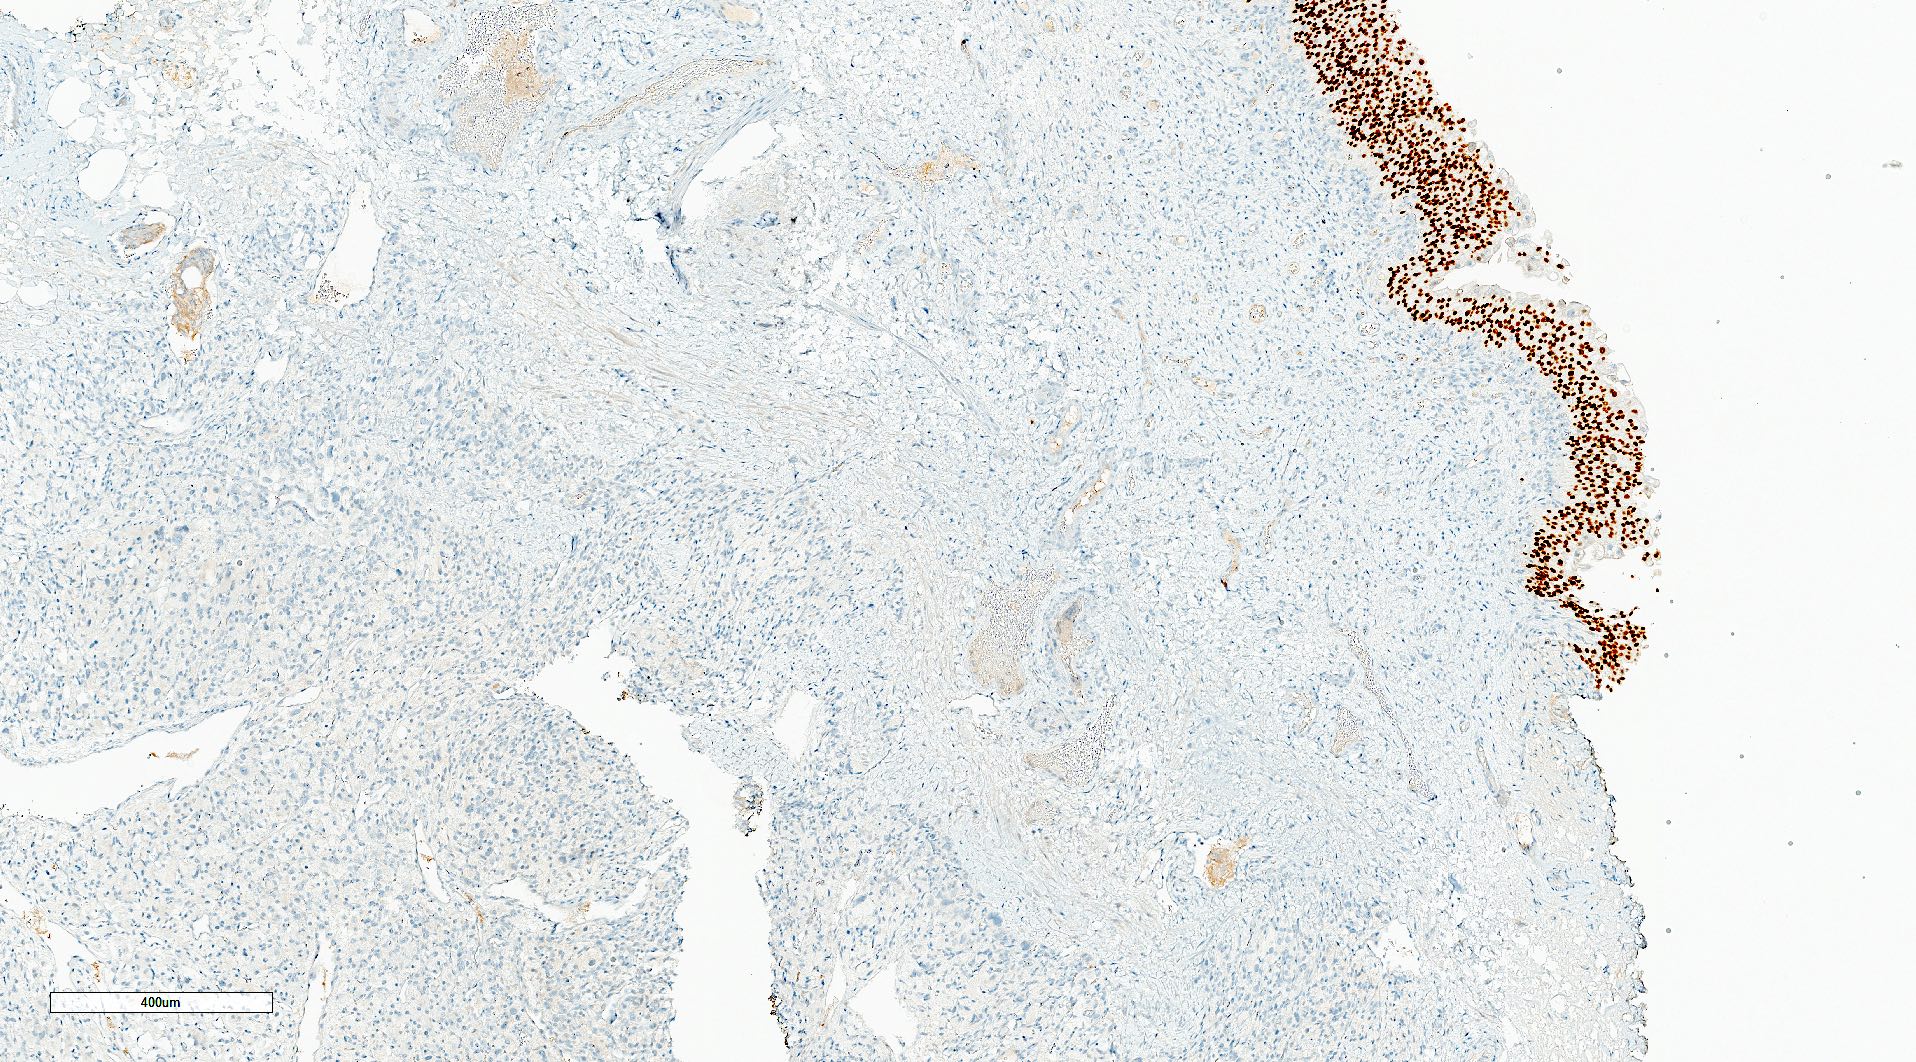

- SDHB germline mutation is the strongest genetic prognosticator of poor outcomes; SDHB immunohistochemistry is routinely used for its identification

- Modified GAPP: based on the same prognostic factors as GAPP with the addition of SDHB loss on IHC (PLoS One 2017;12:e0187398)

- COPPS (composite pheochromocytoma / paraganglioma prognostic score), with unfavorable factors being focal or confluent necrosis, PS100 loss, vascular invasion, SDHB loss, tumor size > 7 cm, capsular invasion, increased mitotic figures and MCM6 (minichromosome maintenance) > 30% (Virchows Arch 2019;474:721)

Microscopic (histologic) images

Contributed by Theodorus H. van der Kwast, M.D., Ph.D., Michelle R. Downes, M.D., Debra L. Zynger, M.D. and David Cohen, M.B.B.Ch., M.D.

- SDHB loss (absence of granular cytoplasmic labeling) if SDHB mutation

- Paraganglioma, SDHB staining intact (see comment)

- Comment: The risk of malignancy in these lesions is estimated at 5 - 15% of cases. Malignant behavior cannot be predicted based on morphology alone and relies on the identification of metastases. Tumors associated with SDHB mutations (loss of SDHB staining) are reported to have an increased risk of metastases.

- Microscopic description: This specimen shows an unencapsulated, monomorphous population of round tumor cells in a nested / zellballen pattern with delicate vascular septa and intervening extravasated red blood cells. It predominantly involves the lamina propria of the bladder but in 1 tissue piece clearly involves muscularis propria. The tumor cells have abundant amphophilic cytoplasm and vesicular chromatin with occasional small nucleoli. There is no necrosis, diffuse growth pattern or vascular space invasion identified. The mitotic count is (maximally) 1/10 high power fields. Immunohistochemistry shows the tumor cells to be positive for GATA3 with strong and diffuse expression of synaptophysin and chromogranin, as well as retention of SDHB staining. The tumor cells are negative for AE1 / AE3, HMWK and p63. The Ki67 proliferation index is < 1%. S100 shows faint nuclear and cytoplasmic staining with occasional sustentacular cells identified.